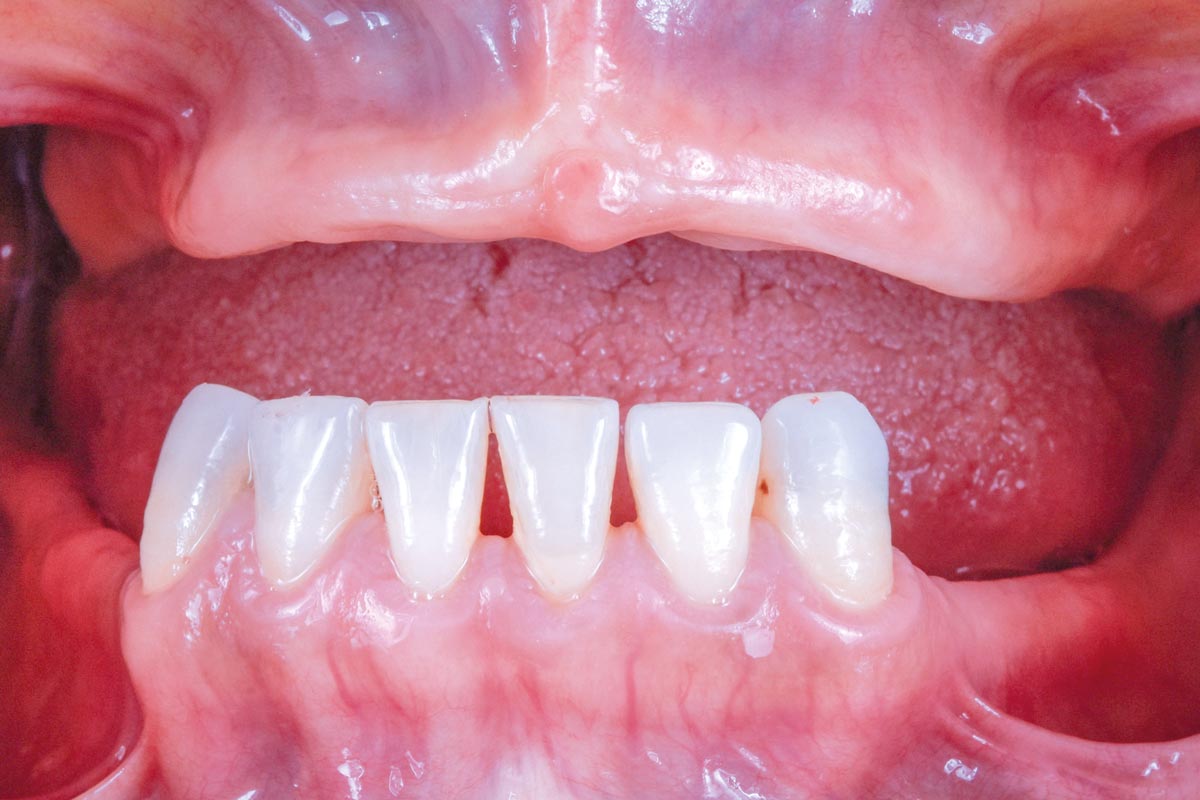

Initial view of the case. Discoloration of 1.1 and mild class I gingival recession